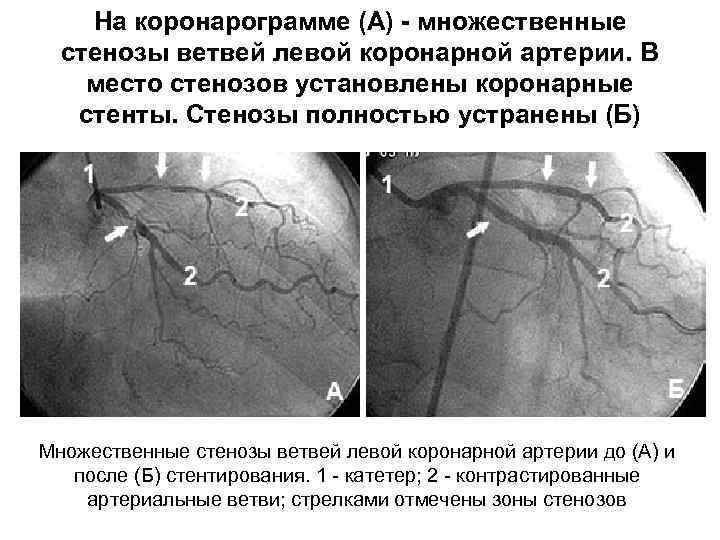

Анатомия коронарных артерий: КТ-изображения